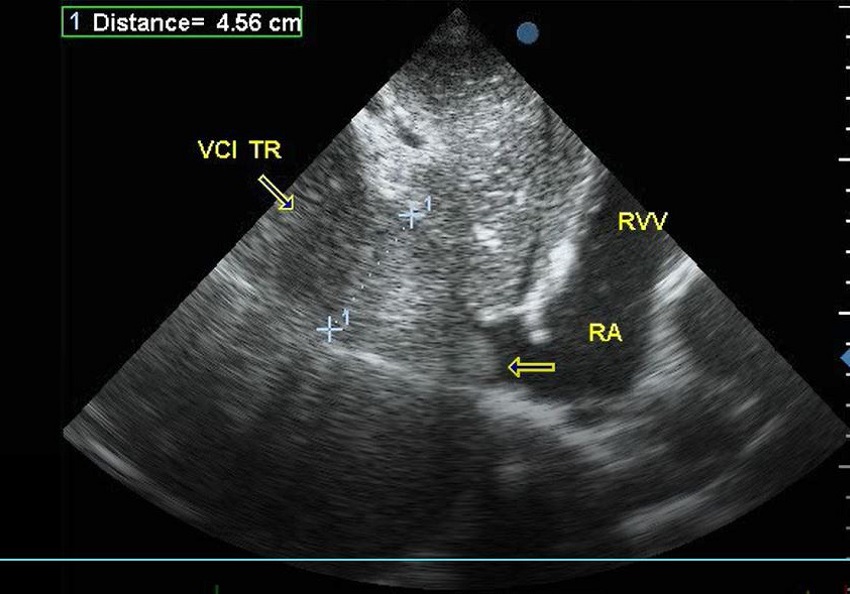

The operation was performed by our team of vascular surgeons. Cardiac surgery team was also assembled assigned to the care of the patient, because the original plan was to do the sterno-laparotomy and partial veno-venous bypass. Following the induction of general anesthesia, internal jugular central line was inserted. In addition, a multiplane TEE probe was placed in the esophagus. Initial TEE examination of the heart confirmed the normal cardiac structures and function without a patent foramen ovale. TEE study was performed with emphasis on the hepatic veins, IVC, right side of the heart, and pulmonary arteries (PAs). The tumor was well visualized in the IVC extending proximal into the RA for male patient and supradiaphragmatic portion of IVC in female patient (Figure 2).

Surgery proceeded with median laparotomy and right subcostal incision for female patient and bilateral subcostal Chevron incision for male patient. Cardio surgical team and cardiopulmonary bypass team were placed on standby. Liver was mobilized, hepatic veins were exposed, and the IVC was isolated (Figure 3). With a Kocher maneuver the infrarenal IVC was exposed. Proximal clamp was placed at the suprahepatic portion of IVC and distally at infrarenal part of IVC. Renal artery and vein were ligated and thereafter infrarenal IVC was clamped and opened at the level of renal vein (right for female and left for male patient). Under the surveillance of TEE, the right atrium thrombus immediately retracted in the supradiaphragmatic part of IVC in male patient and in infradiaphragmatic-suprahepatic portion of IVC in female patient, and, subsequently, thrombectomy was done. After the extraction of the thrombus the nephrectomy was done. On the control TEE there was no remnant thrombus in IVC nor the evidence of distal embolization. The site of thrombectomy on IVC was reconstructed with direct suture in both cases. Due to adhesions between spleen and the left kidney, the spleen was injured in male patient and subsequent splenectomy was done. During the operation the female patient bleed out 2500ml and the male 1500ml. One thousand ml of autologous blood was returned with Cell saver for female patient and 600ml for male patient. The intraoperative course was uneventful and the patient went to the ICU in stable condition. The gross specimen was inspected and found no missing a tissue fragment (Figure 4). Further postoperative TEE revealed no tumor masses in right atrium or retrohepatic part of IVC. Postoperative recovery was uneventful as the first follow-up visit after one month for both patients. Pathohistology two weeks after the operation showed the confirmation of renal cell carcinoma both Fuhrman grade III.

TEE has major effects on the decision-making process in surgical and anesthetic management. TEE can also demonstrate the tumor mobility, whether it is fragile and/or adherent to the IVC. A fragile tumor has a higher risk of pulmonary embolism, and adherence of the tumor to the IVC wall may result in an incomplete resection of the tumor or vascular injury when using an occlusion balloon catheter. TEE imaging can determine whether it will be possible to bring the thrombus down with the balloon or not, and also provide information about the precise location and size of the balloon. Because TEE visualized a mobile and oscillating thrombus, we decided to remove it by using an occlusion balloon catheter. We removed the thrombus successfully by this simple technique with minimum hepatic mobilization for the thrombectomy. It should be also monitored by the operators directly on the surgical field. Intraoperative real-time TEE monitoring can be provided by anesthesiologists without interruption of the surgical procedure, and we regard this as one of the most important advantages of TEE monitoring. Most importantly, the real-time TEE monitoring allowed us to perform this intervention safely. Fortunately, no evidence of pulmonary embolism was found in our two cases. Nevertheless real-time TEE can provide rapid recognition of massive pulmonary embolism. TEE can reveal the sudden disappearance of the tumor head, presence of the thrombus in the pulmonary artery, or any sign of right heart dysfunction. Intraoperative TEE is also useful in anesthetic management to evaluate the left ventricular volume (LV) and function. Massive bleeding and decreased venous return due to the IVC clamp can be immediately treated with volume loading according to the LV volume assessed by TEE.